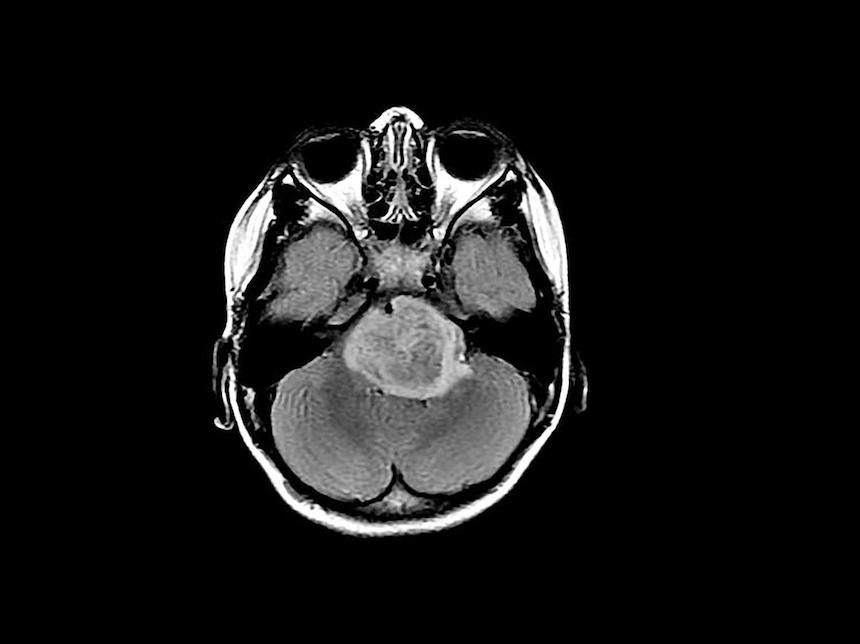

High-grade gliomas cause more deaths than any other form of brain cancer, partly due to the extreme difficulty surgeons have in removing all of the tumor cells. This leaves clinicians dependent on traditional chemotherapy and radiation treatments that have limited success. Depending on the specific subtype of tumor, more than three-quarters of patients die within five years, and for the most common childhood glioma that number exceeds 99 percent.

In the current study, the researchers extracted tumor cells from patients with several varieties of high-grade gliomas and inserted them into the brains of two breeds of mice, one normal and one lacking the gene that produces neuroligin-3. In the latter, none of the tumors grew substantially for four and a half months and roughly half remained stagnant after six months, whereas tumors grew markedly in the mice with an intact neuroligin-3 gene. Further experiments suggested neuroligin-3 triggers a series of chemical reactions that stimulates multiple signaling pathways involved in glioma growth, causing the tumors to expand.